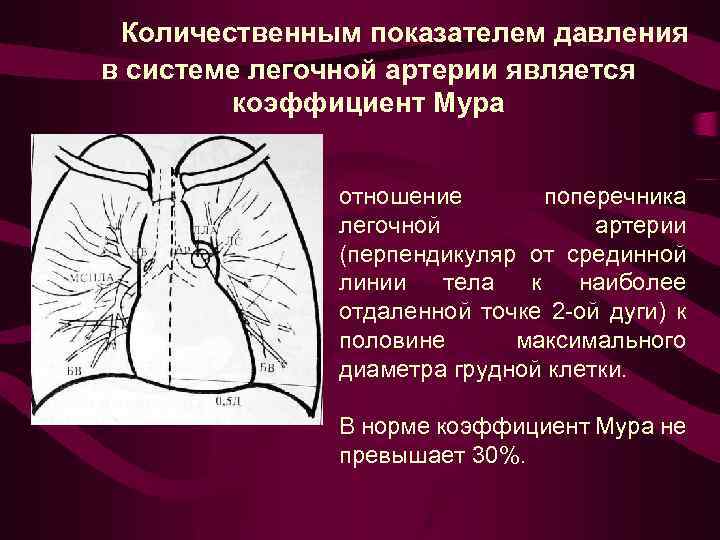

Количественным показателем давления в системе легочной артерии является коэффициент Мура отношение поперечника легочной артерии (перпендикуляр от срединной линии тела к наиболее отдаленной точке 2 -ой дуги) к половине максимального диаметра грудной клетки. В норме коэффициент Мура не превышает 30%.

Количественным показателем давления в системе легочной артерии является коэффициент Мура отношение поперечника легочной артерии (перпендикуляр от срединной линии тела к наиболее отдаленной точке 2 -ой дуги) к половине максимального диаметра грудной клетки. В норме коэффициент Мура не превышает 30%.